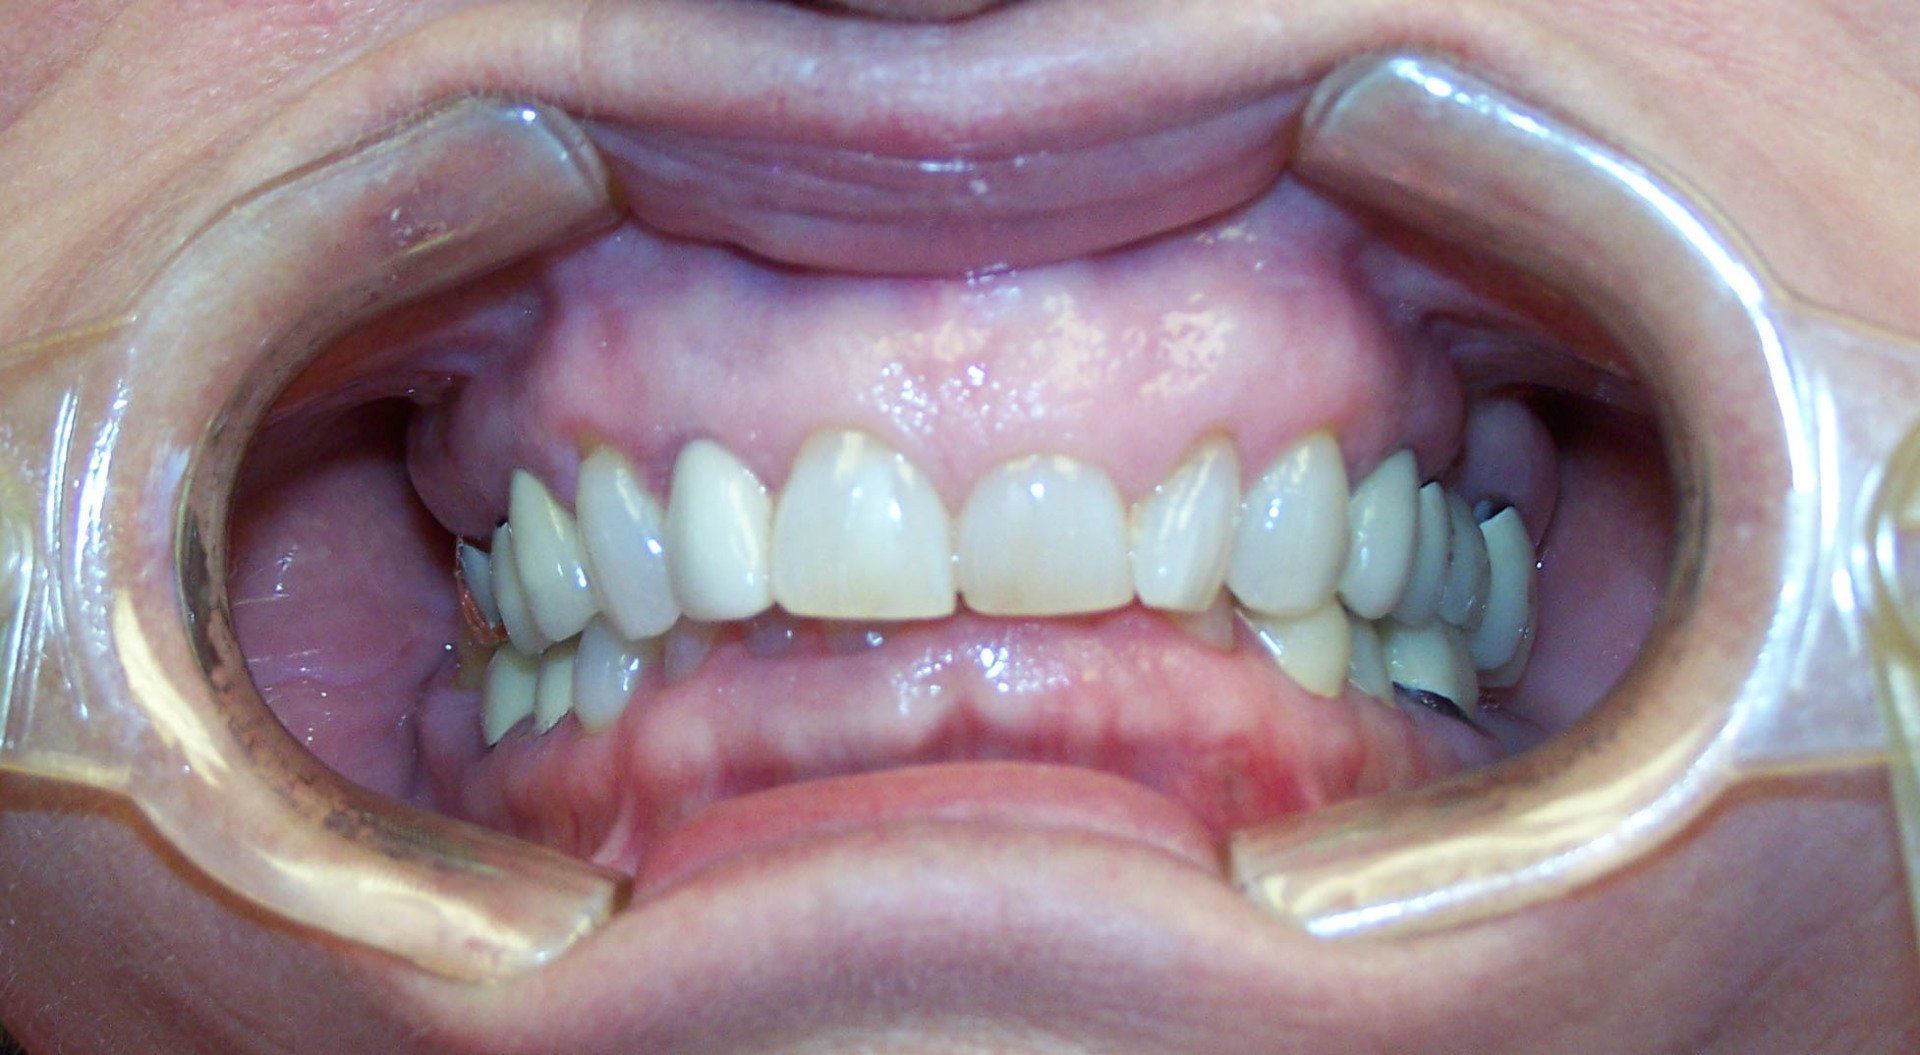

Ally After

Holly After

Johnson After

Karen After

Nancy After

Ralph After

Steve After